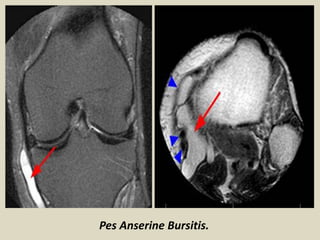

Pes Anserine Bursitis

The Pes anserine bursa separates the Pes anserine tendons,

consisting of the distal sartorius, gracilis, and semitendinosus

tendons, from the subjacent distal portion of the tibial collateral

ligament and the bony surface of the medial tibial condyle.

Anserine bursitis results from overuse, especially in runners.

On MRI, Pes anserine bursitis appears as an oblong multiloculated

fluid collection seen along the anserine tendons on the

posteromedial aspect of the knee. This is best appreciated on T2W

axial images. It is commonly confused with a popliteal cyst; the Pes

anserine bursa is located posteriorly and medially along the

semitendinosus, whereas the popliteal cyst is located more often in

the midline posteriorly. Also, Pes anserine bursae are small in size;

they do not extend into the thigh and never show communication

with the knee joint, whereas a popliteal cyst can extend into the

thigh and may or may not communicate with the knee joint.

a) Axial line diagram and (b) axial magnetic resonance image showing Pes anserine bursitis.

Pes anserine bursitis. A 32-year-old female presented with pain along the posteromedial aspect

of the knee: Coronal proton density (A) and axial T2W (B) images show a distended Pes anserine

bursa (arrows). The Pes anserine tendons (arrowhead in B) are seen inferior to the bursa.

Pes Anserine Bursitis.